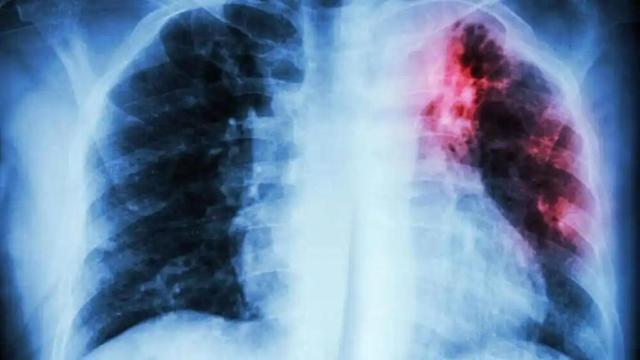

Cáncer de pulmón